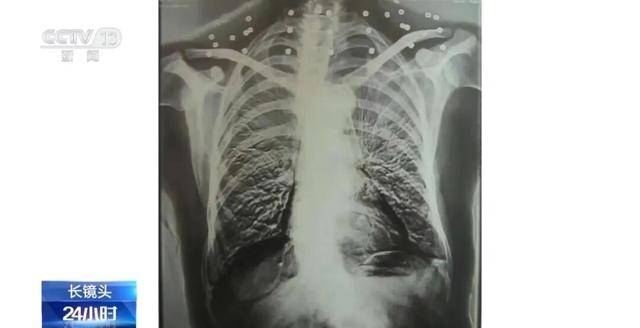

这张图片是82岁吴以先老人的CT照,当初拍片时,医生说,“老先生,您要把项链取下来再做CT。”

吴以先说,“我从来没戴过项链,你看会不会是弹片?”由此,引出了老人一段不平凡的往事。

20年前,吴以先做CT检查时,由于颈部有许多弹片,医生误将弹片认作是他戴的项链,于是提醒他要把项链取下来,再做检查。

实际上,在吴以先的颈部和腹部,共分布着33个弹片。